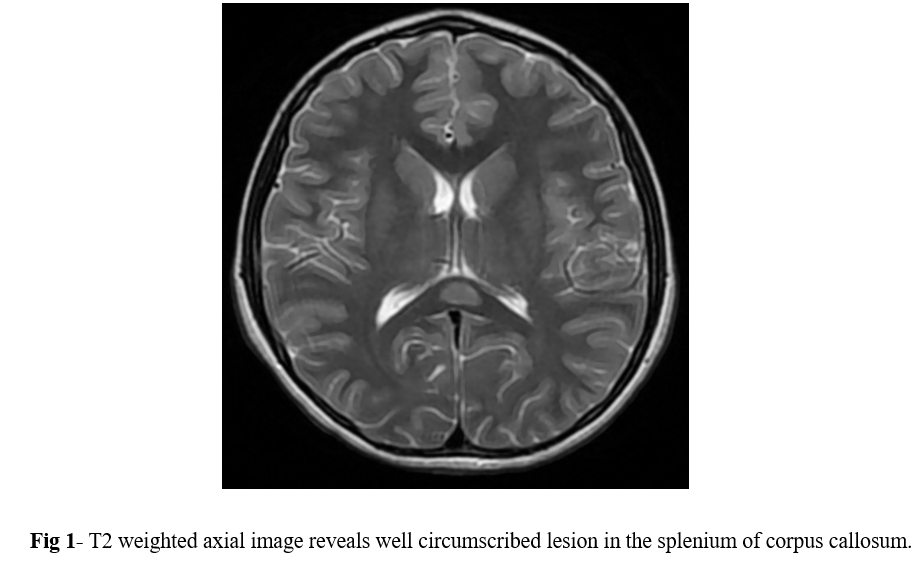

MRI of the brain with contrast was performed using 1.5 tesla scanner (GE Medical System). An oval well-circumscribed lesion was noted in the splenium of the corpus callosum in the midline (Figure 1). The lesion displayed restricted diffusion with low ADC values (Figures 2 and 3). No evidence of mass effect or perifocal edema was seen. No evidence of abnormal post-contrast enhancement was noted (Figure 4). No lesions are seen in the periventricular white matter and in the subcortical U fibers. In view of the clinical history and morphology of the lesion was read as reversible splenial lesion syndrome (RESLES). The differential diagnosis that were considered included ADEM, multiple sclerosis, encephalitis and glial tumor.

Figure 1